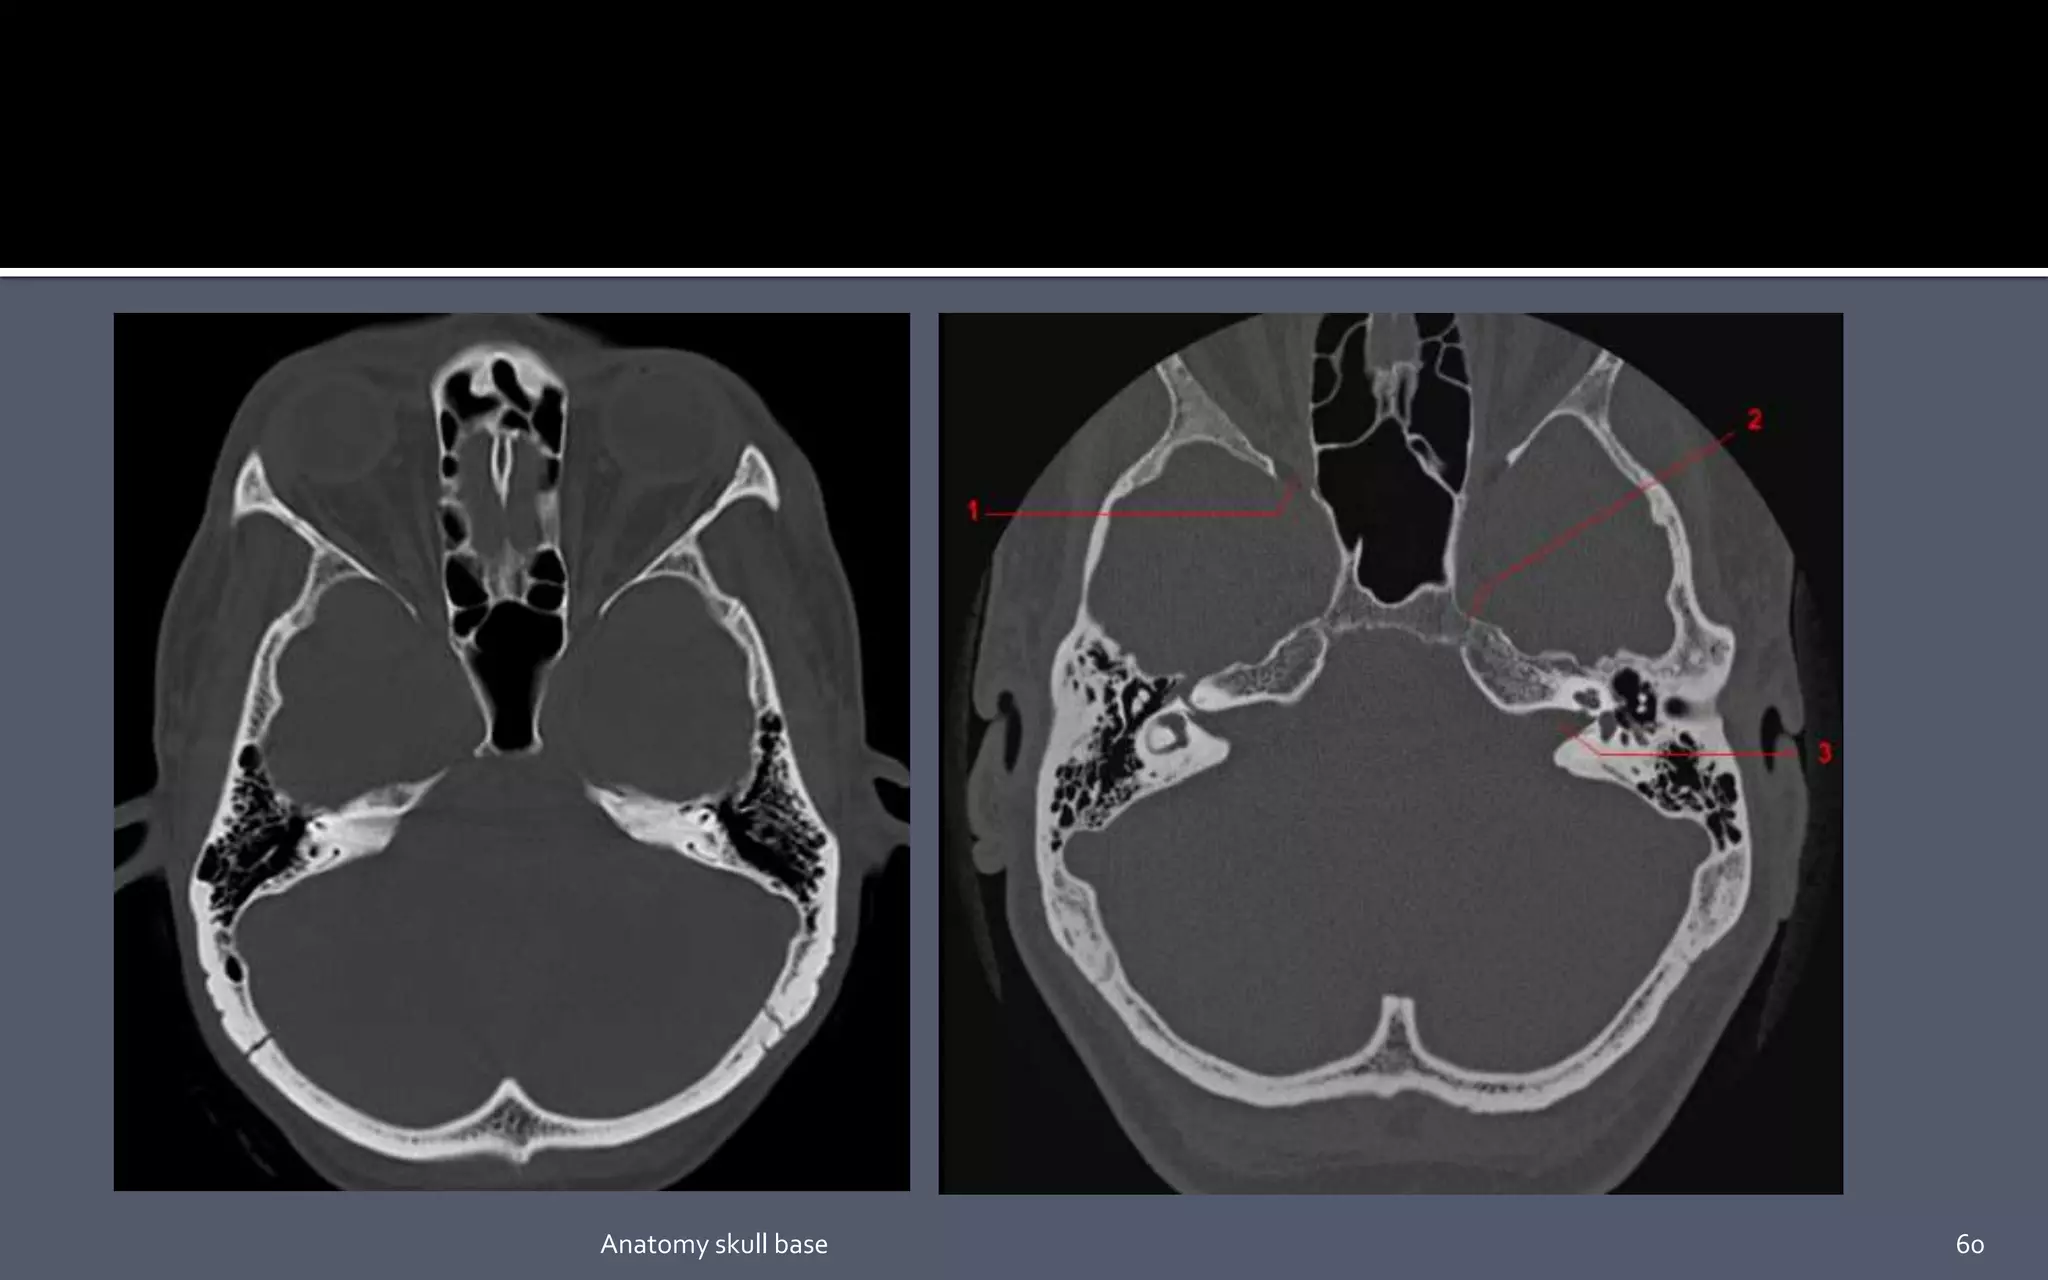

• #20 The medial red lines pass in the medial aspect of the petroclival synchondrosis (long white arrows). The lateral red lines pass immediately lateral to the foramen ovale. (short white arrow).

• #49 1. Petro-occipital fissure. 2. Petrosphenoid suture. 3. Tympanomastoid suture. 4. Sphenosquomaous suture. 5. Sphenozygomatic suture.